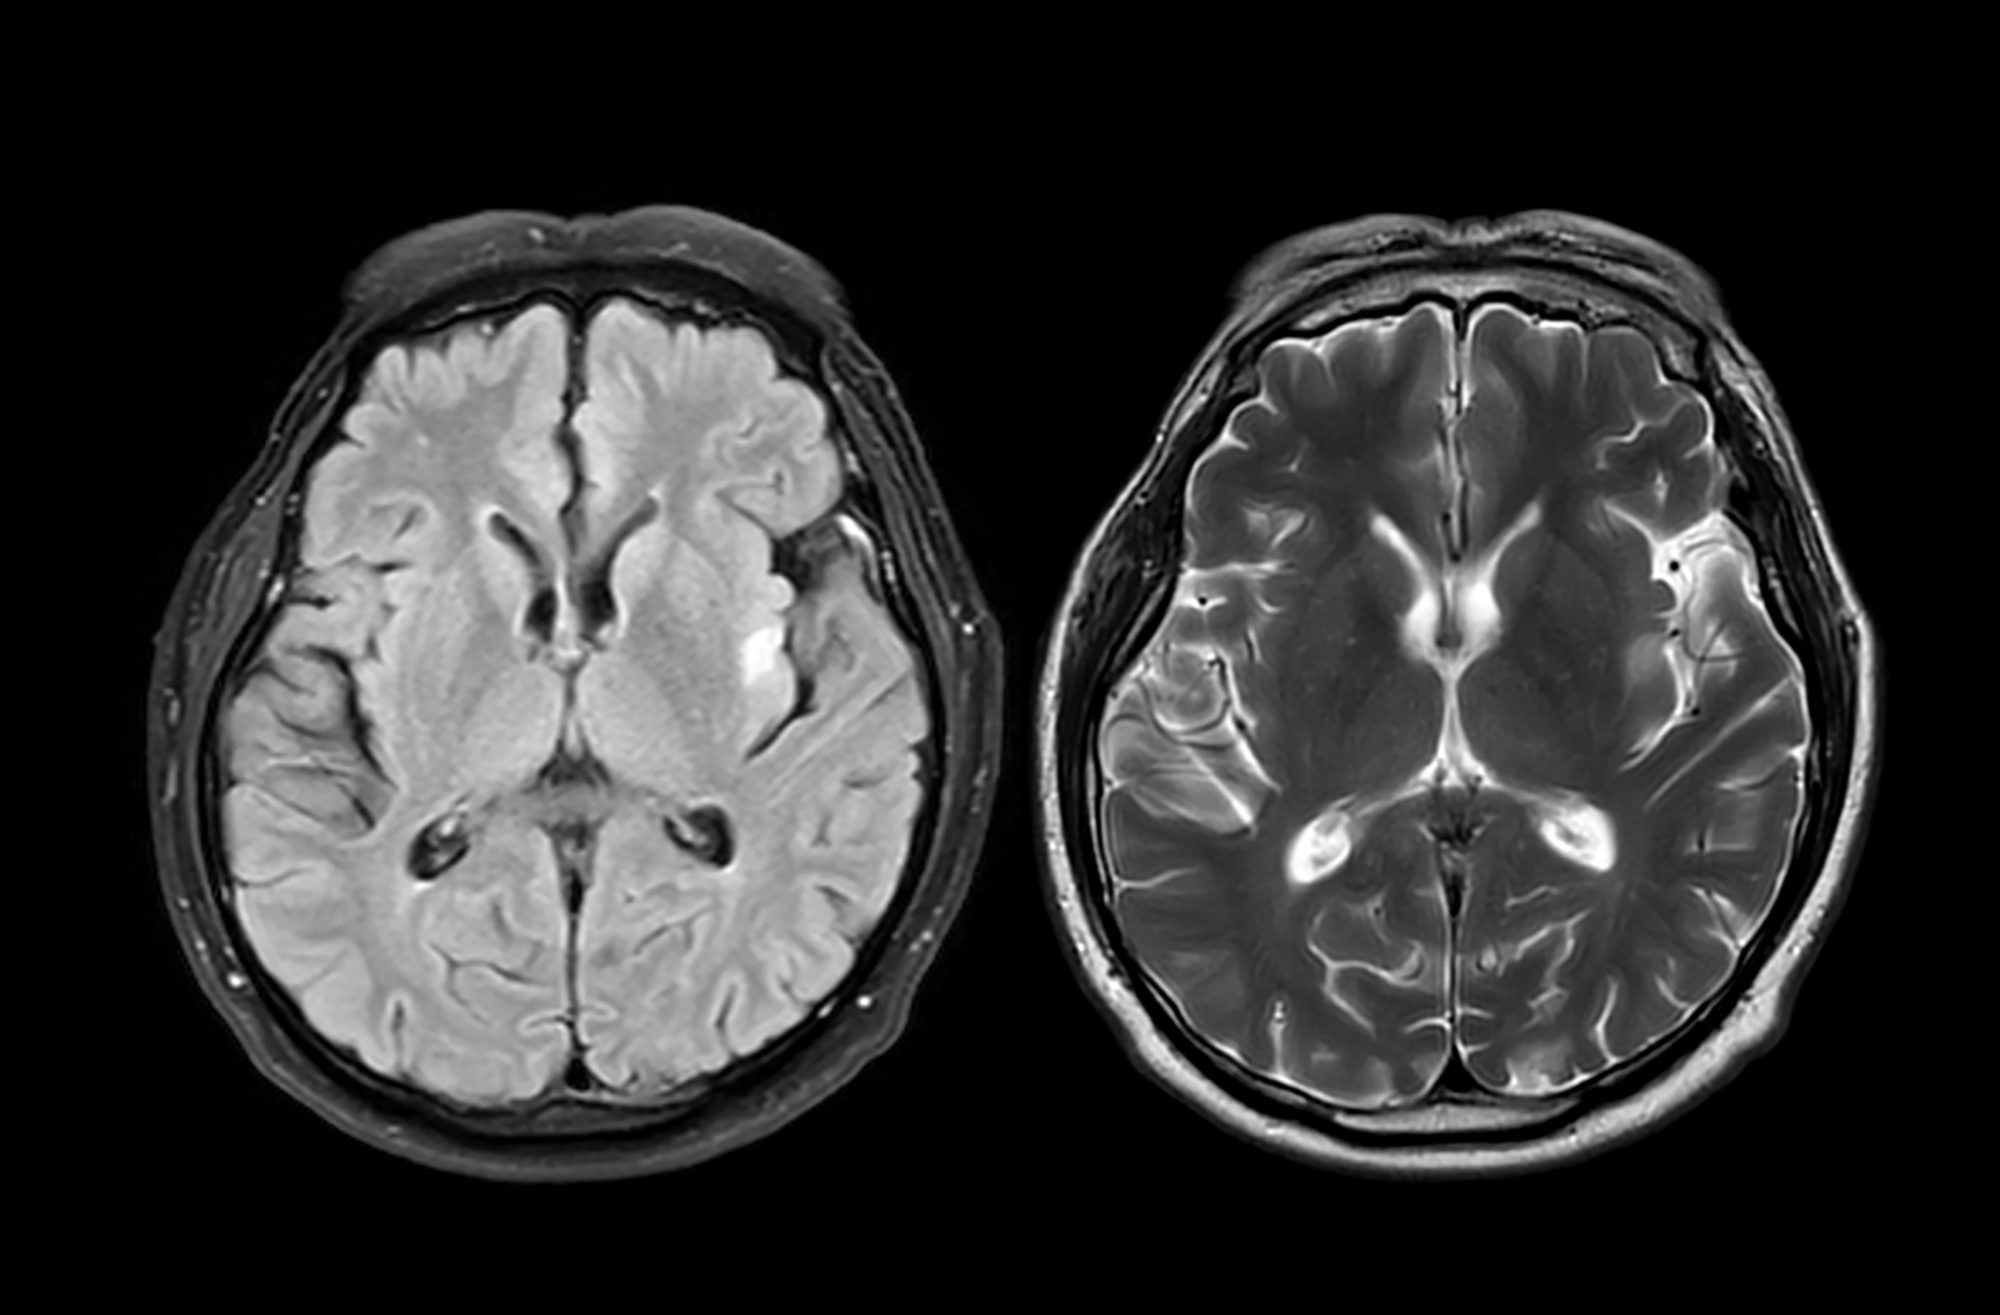

For more than a century, doctors have recognised Parkinson’s by the presence of large protein deposits called Lewy bodies. But scientists have suspected that minor, earlier-forming oligomers may cause damage to brain cells. Until now, these oligomers were too small to see – just a few nanometres long.

A new technique, developed by the researchers, is called ASA-PD (Advanced Sensing of Aggregates for Parkinson’s Disease), and uses ultra-sensitive fluorescence microscopy to detect and analyse millions of oligomers in post-mortem brain tissue.

Since oligomers are so small, their signal is very weak. ASA-PD works by maximising the signal whilst decreasing the background, dramatically boosting sensitivity to the point where individual alpha-synuclein oligomers can be observed and studied.

The team analysed post-mortem brain tissue samples from people with Parkinson’s and compared them to healthy individuals of similar age. They found that oligomers exist in both healthy and diseased brains, including those with Parkinson’s. However, the main difference between disease and healthy brains was the size of the oligomers, which were larger, brighter and more numerous in disease samples, suggesting a direct link to Parkinson’s disease progression.